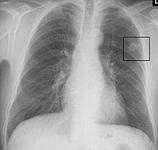

老年人肺癌治療

• 老年人肺癌

628健康網為您分享有關老年人肺癌的癥狀,老年人肺癌的治療方法,老年人肺癌的預防知識,老年人肺癌的癥狀圖片,老年人肺癌...